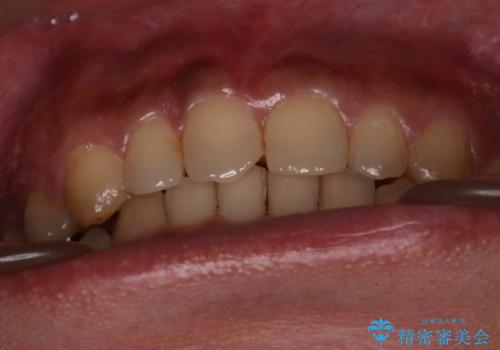

【モニター】インビザライン 前歯の捻れを治したい

- 30代男性

マウスピースをしっかり使用していただいたことで、主訴である前歯のがたつきも改善され

リファイメントも1回のみで治療を終了することが出来ました。